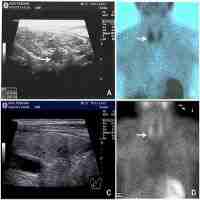

| Abstract | Background There has been a notable shift towards the diagnosis of less severe and asymptomatic primary hyperparathyroidism (PHPT) in developed countries. However, there is a paucity of recent data from sub-Saharan Africa (SSA), and also, no reported data from SSA on the utility of intra-operative parathyroid hormone (IO-PTH) monitoring. In an earlier study from Inkosi Albert Luthuli Central Hospital (IALCH), Durban, South Africa (2003–2009), majority of patients (92.9%) had symptomatic disease. The aim of this study was to evaluate the clinical profile and management outcomes of patients presenting with PHPT at IALCH. Methods A retrospective chart review of patients with PHPT attending the Endocrinology clinic at IALCH between July 2009 and December 2021. Clinical presentation, laboratory results, radiologic findings, surgical notes and histology were recorded. Results Analysis included 110 patients (87% female) with PHPT. Median age at presentation was 57 (44; 67.5) years. Symptomatic disease was present in 62.7% (n:69); 20.9% (n:23) had a history of nephrolithiasis and 7.3% (n:8) presented with previous fragility fractures. Mean serum calcium was 2.87 ± 0.34 mmol/l; median serum-PTH was 23.3 (15.59; 45.38) pmol/l, alkaline phosphatase 117.5 (89; 145.5) U/l and 25-hydroxyvitamin-D 42.9 (33.26; 62.92) nmol/l. Sestamibi scan (n:106 patients) identified an adenoma in 83.02%. Parathyroidectomy was performed on 84 patients with a cure rate of 95.2%. Reasons for conservative management (n:26) included: no current surgical indication (n:7), refusal (n:5) or deferral of surgery (n:5), loss to follow-up (n:5) and assessed as high anaesthetic risk (n:4). IO-PTH measurements performed on 28 patients indicated surgical success in 100%, based on Miami criteria. Histology confirmed adenoma in 88.1%, hyperplasia in 7.1% and carcinoma in 4.8%. Post-operative hypocalcaemia developed in 30 patients (35.7%), of whom, 14 developed hungry bone syndrome (HBS). In multivariate analysis, significant risk factors associated with HBS included male sex (OR 7.01; 95% CI 1.28, 38.39; p 0.025) and elevated pre-operative PTH (OR 1.01; 95% CI 1.00, 1.02; p 0.008). Conclusions The proportion of asymptomatic PHPT has increased at this centre over the past decade but symptomatic disease remains the dominant presentation. Parathyroidectomy is curative in the majority of patients. IO-PTH monitoring is valuable in ensuring successful surgery. |